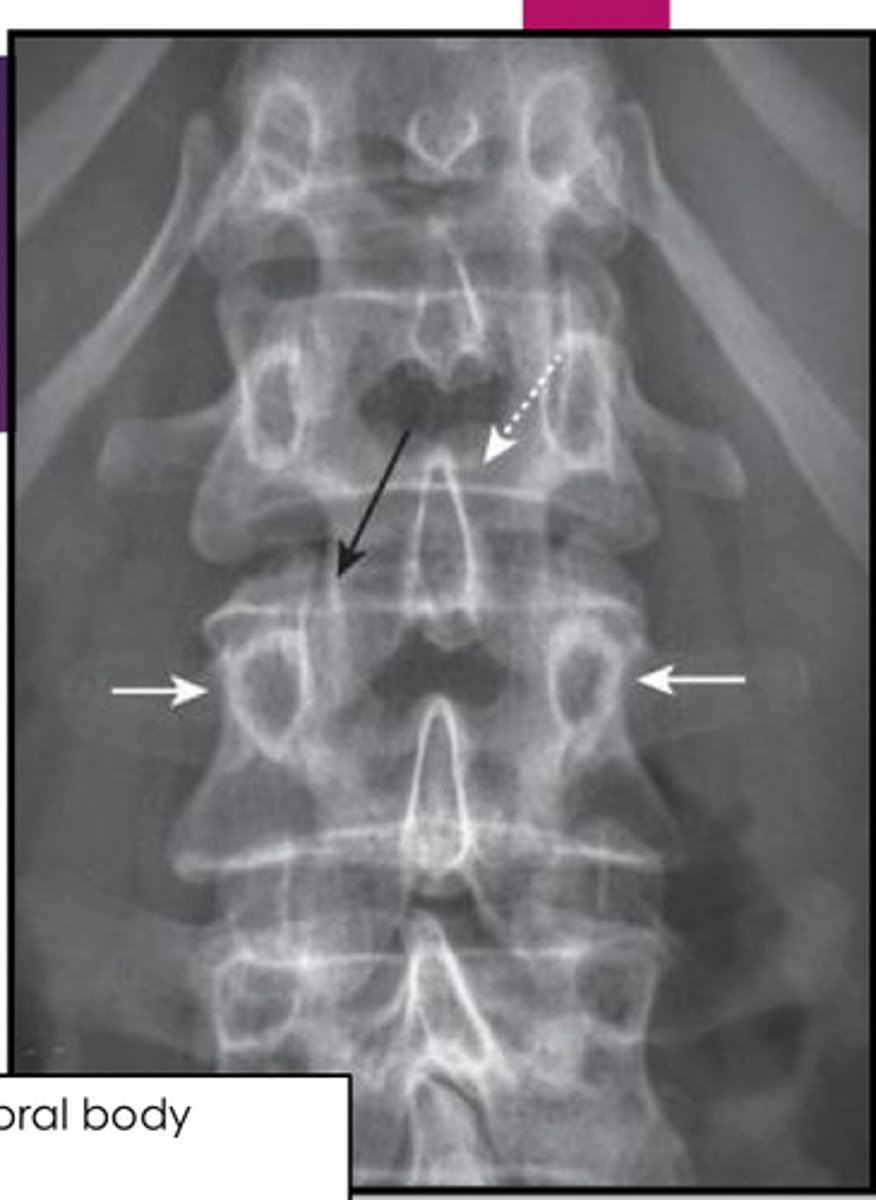

normal L/S xray

white arrows: 2 pedicles on side of vertebral body

white dotted arrow: spinous process

black arrow: facet joint